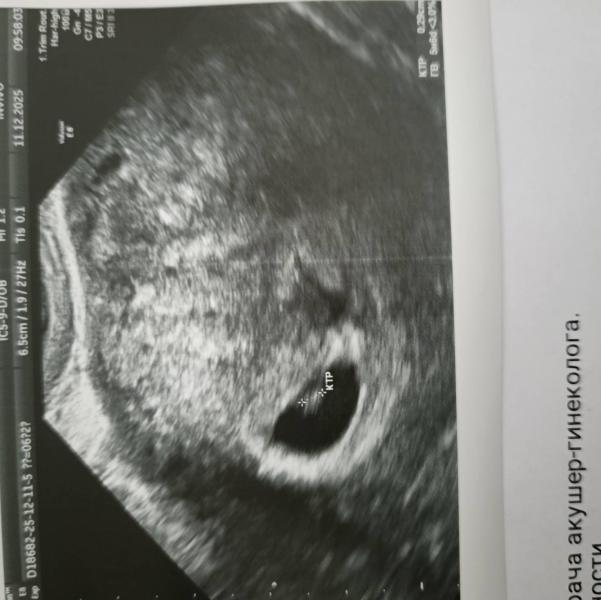

Здравствуйте 🌸 слушали сердечко ?) завтра еду на узи, будет 6 недель ровно. Переживаю , мало ли не увидят, не услышат 🙈

Я на 5 недель 6 дней узи делала еще сердечко не слышно

Сказали ближе к 7 недели приходите